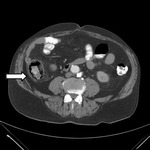

Abscesso hepático: tomografia computadorizada (TC) do abdome sem contraste mostrando um enorme abscesso hepático com gás (seta)

Adaptado de BMJ Case Reports 2009 (doi:10.1136/bcr.08.2008.0638)